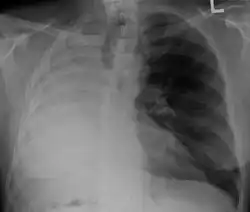

| Left tension pneumothorax with a large, well-demarcated area devoid of lung markings with tracheal deviation and movement of the heart away from the affected side. |